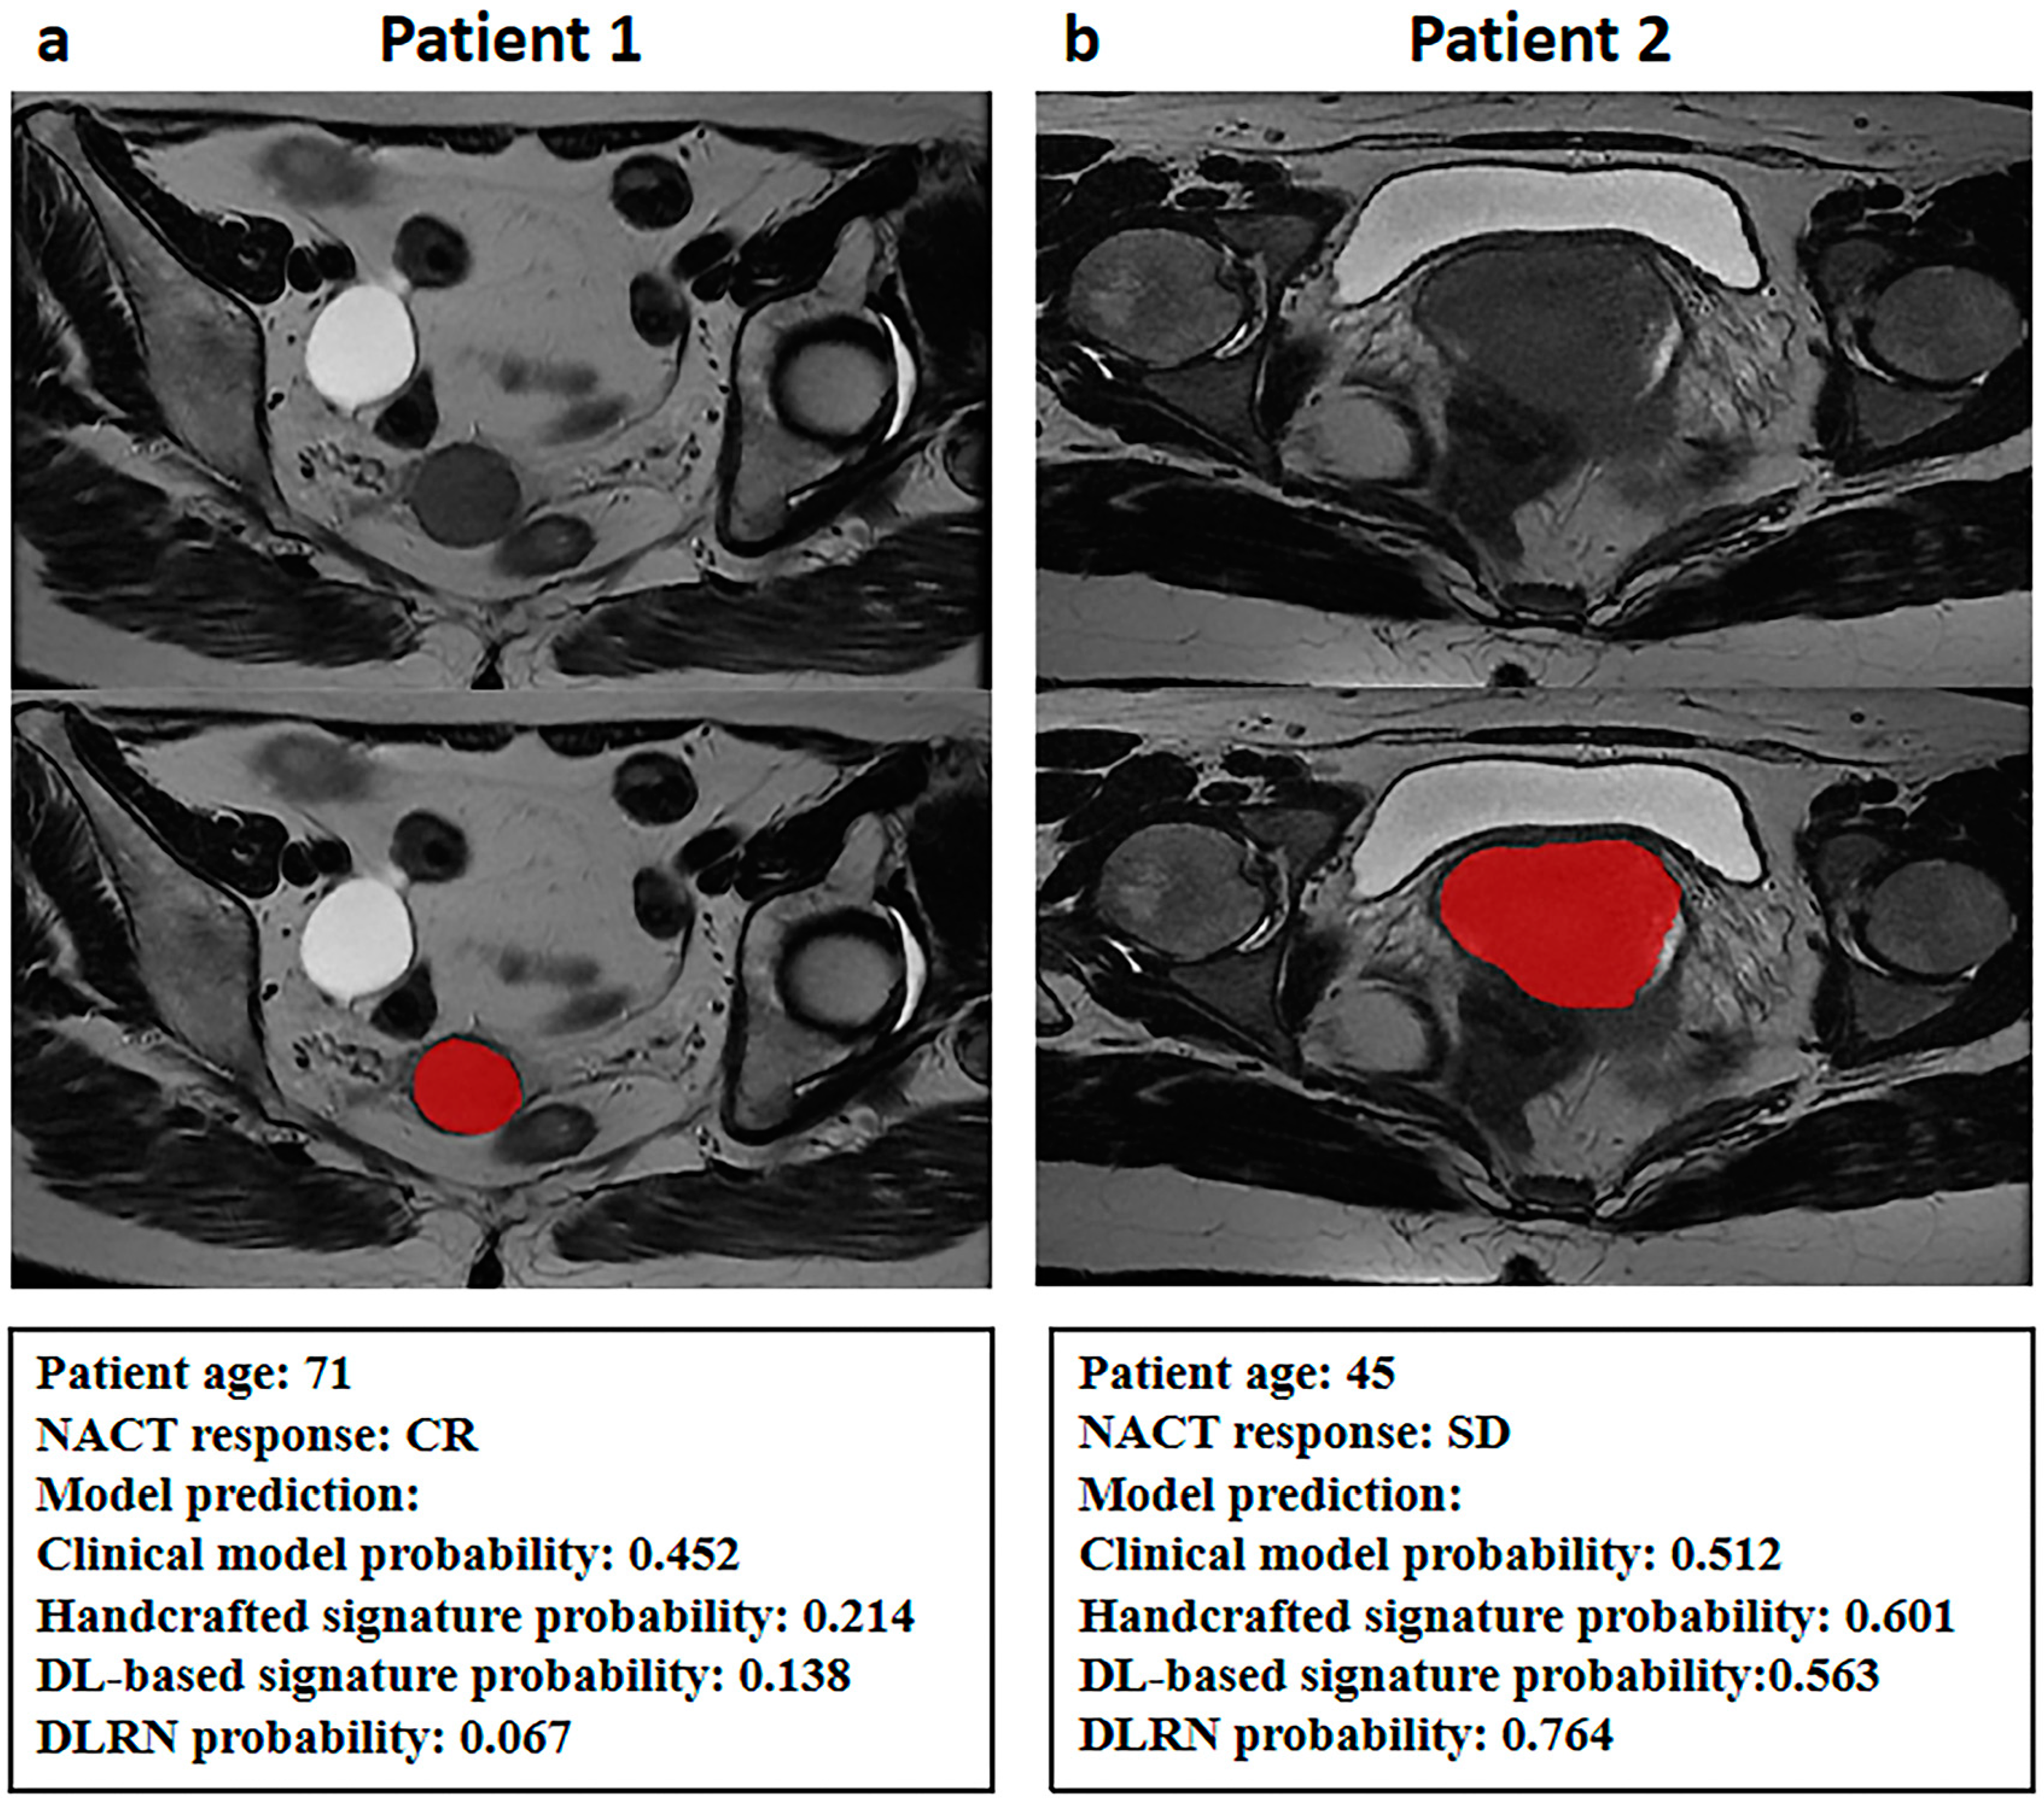

| Index | β | Odds Ratio (95% CI) | Multivariate p Value |

|---|---|---|---|

| Clinical model probability | 1.297 | 3.660 (1.109–12.082) | 0.033 * |

| Handcrafted radiomics signature probability | 1.087 | 2.965 (1.796–4.893) | <0.001 * |

| DL-based radiomics signature probability | 1.157 | 3.181 (1.845–5.486) | <0.001 * |

| Intercept | −0.547 | - | 0.078 |